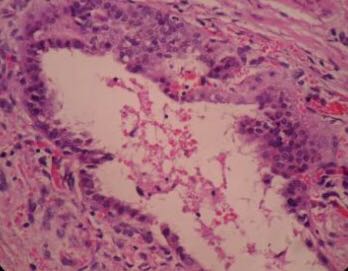

诊断:会阴肿物(子宫内膜异位症?) 治疗:阴式会阴子宫内膜异位症病灶切除术。术中见会阴体左侧(相当于外阴4点-5点处),可及约3X3厘米大小质韧肿物,界限不清,肿物已经侵入肛提肌及肛门括约肌。术中剖检所切除肿物见其中紫蓝色出血病灶,边缘一圈正常组织,证实肿物切除完全,冰冻病理回为子宫内膜异位症。

会阴内异症是发生在盆腹腔以外的一种内异症,其临床特点与盆腔内子宫内异症相差甚远,发生率低,潜伏期长。会阴瘢痕内异症是较少见的一种,其发生可能是蜕膜化的子宫内膜细胞种植在开放的会阴切口上,支持种植学说会阴内异症的早期诊断和治疗很重要,在病灶进行性侵犯肛门括约肌及其周围组织之前发现可使治疗充分彻底。会阴内异症的治疗方法有多种,手术治疗同时辅助药物治疗是首选方法。手术切净以至少切除病灶外0. 5 ~ 1 cm 的组织为标准。肛门括约肌的受累密切关系到治疗与预后。侵犯肛门括约肌的会阴内异症复发率高,且多由于不完全切除导致。如能于术前准确评估肛门括约肌的受累程度,估计手术难度,做好充分术前准备,有望提高病灶的完整切除率,减少术后复发。